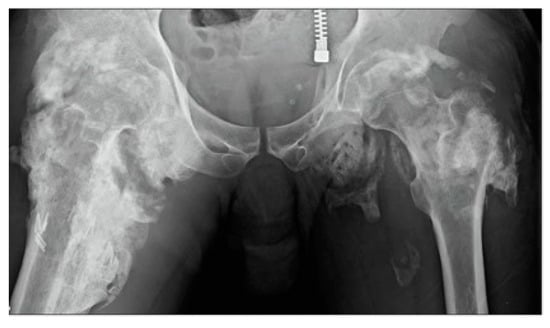

The current classification schemes for assessing tHO include the planar projection of mineralization using a four-level radiological classification [116] or checkerboard-like patterns within the muscle regions observed via computer tomography (CT). These radiographic-based assessments involve global estimates of the degree of soft tissue mineralization [117], but they do not effectively detect pre-mature bone formation, limiting its use to monitoring the progress of tHO and implementing early-stage diagnosis and timed therapeutic strategies at the bedside. Figure 3 shows an example of radiographic imaging from our prior case with massive bilateral HO in an immobilized patient with SCI [118]. Furthermore, tHO is associated with elevated serum ALP, CPK, C-reactive protein (CRP), erythrocyte sedimentation rate (ESR), and prostaglandin E2 (PGE2) [119], which are reliable and sensitive indicators of the tHO formation process following spinal cord injury. Elevated levels of serum CPK are an indicator of HO severity, while the stabilization of ALP is contradictory with HO maturation [120,121]. Table 2 shows the lab test characteristics of tHO and non-tHO patients. Despite the fact that the differences observed in serum biomarker levels in these studies suggest their ability to aid in HO diagnosis, further exploration into their clinical use will be important for solidifying our understanding of their utility.

Figure 3. Radiographic-based diagnostic imaging represented massive bilateral peri-articular HO in an immobilized patient with SCI [118].